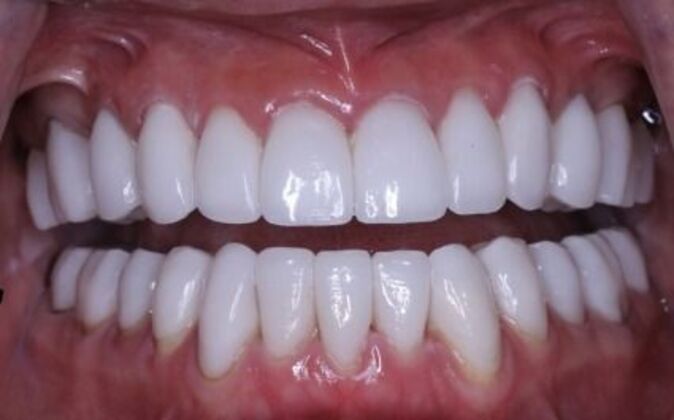

Full Mouth Reconstruction: Risa

Full mouth reconstruction. When you see a client at a young age with so much dental work to begin with you consider your options carefully. You need to be aggressive in approach and conservative in maintaining as much of the healthy tooth structure. Have to consider the age of a patient whenever you embark on a major dental work especially when it involves redoing everything, repositioning and re-establishing a brand new bite position and correcting the inflammatory gum response from previous dental work. You cannot approach a case like this with a limited treatment plan that only addresses a few teeth. If this case is treated one tooth at a time you may leave the patient a “dental cripple”. By that I mean that this patient will constantly be at dental offices for the rest of her life addressing one broken down tooth after another until a cascading domino effect will render all the teeth in a hopeless condition. Here is a situation where we are dealing with multiple problems 1-bite collapse and malfunction 2-gum disease exacerbated by poorly fitting crowns 3-decaying teeth affecting the health of the roots This case had to consider all of these issues. Must understand that this patient is very young and has many years ahead of her so the dentistry has to be done meticulously, conservatively,aggressively and expeditiously. It’s a tough balancing act but as dentists we need to be realistic about our treatment objectives and have a proper plan that addresses dental breakdown. We were able to achieve the esthetic and functional concerns of the patient. Although we felt the color of the teeth were too bright. We do need to consider patients desires since they need to live with this for the rest of their lives and ultimately they need to be happy